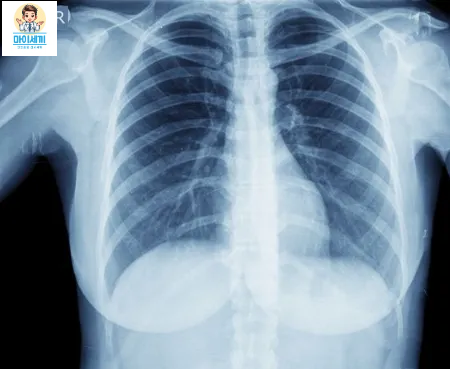

- 3. 흉부 X-레이: 폐 내 이상 소견을 확인하여 결핵 감염의 증거를 찾습니다. 결핵의 전형적인 X-레이 소견에는 폐에 나타나는 음영이나 기타 비정상적인 변화가 포함될 수 있습니다.

폐결핵 진단은 피부 반응 검사, 혈액 검사, 흉부 X-레이, 객담 검사 등을 통해 이루어집니다.